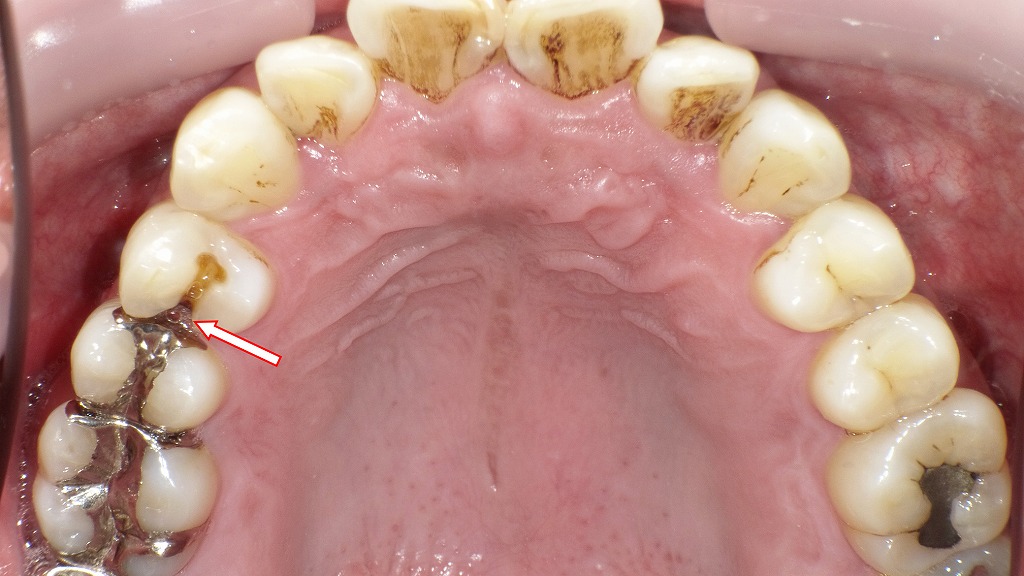

🚨銀歯(ブリッジ)が取れて放置した症例

この画像は、上顎右側の口腔内写真です。以下のように説明できます。

🦷 状況の概要

- 右上4番・5番・6番に装着されていた保険のブリッジが脱離しています。

- 右上4番(第一小臼歯)は生活歯で、歯質は健全に保たれています。

- 一方、右上6番(第一大臼歯)は、被せ物の内部で虫歯が進行し、C4(歯冠崩壊)の状態になっています。

🔍 詳細な所見

- 右上4番:歯冠が健全に残り、歯髄反応のある生活歯。支台歯として再利用可能。

- 右上5番:すでに欠損しているためブリッジのポンティックとして対応。

- 右上6番:金属冠が外れた後、歯根が露出し、内部に深い虫歯を確認。歯質が大きく失われており、抜歯が必要な状態。

⚠️ 臨床的判断

- 右上6番はC4の虫歯であり、保存不可能な可能性が高い。抜歯後はインプラント、部分入れ歯などの補綴的対応が必要です。

- 右上4番は健全なため、単冠の支台歯として再利用できる見込みがあります。